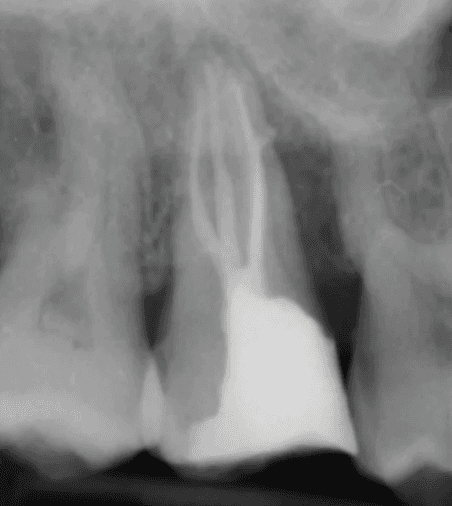

KREENA'S CASES